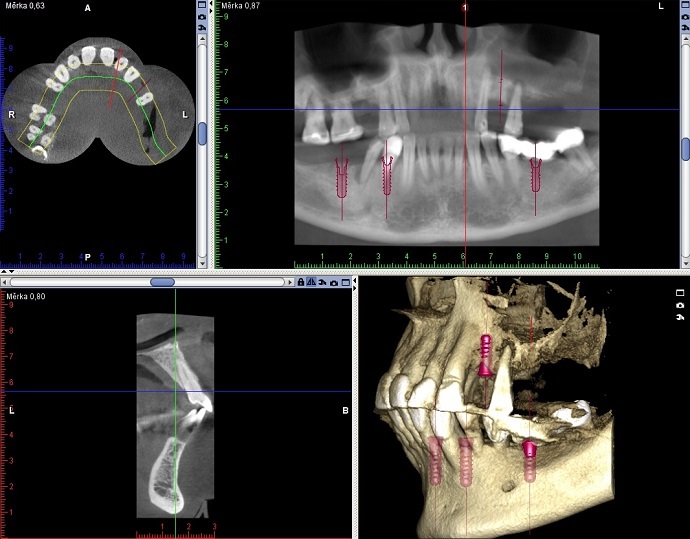

Jako doplňkové vyšetření kosti v okolí zubu může být indikováno CBCT (cone been computed tomography) před chirurgickými výkony, při složité anatomii kořenového systému zubů, obtížně čitelné nálezy na 2D RTG snímcích atd.

Foto 6-7: Zhotovení CBCT v rentgenové místnosti. Výsledný snímek u jiného pacienta.